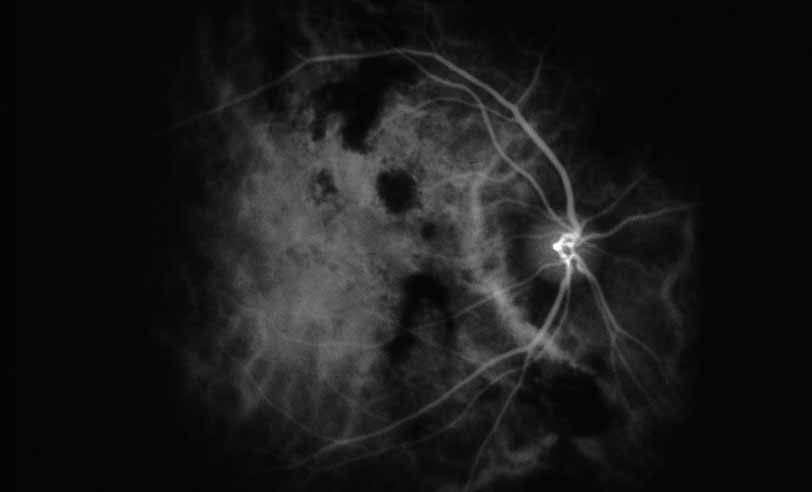

A third instance in which fluorescein angiography concentrating on the optic nerve may be helpful is in eyes with vascular engorgement of the optic nerve, especially with media opacities. Fluorescein angiography may help the clinician distinguish abnormally leaking capillaries from neovascularization. In acute multifocal hemorrhagic retinal vasculitis, optic nerve involvement is common in the early stages of the disease, 47 with optic nerve disc neovascularization seen later (see Figs. 10, 11, 12, and 13). Another fluorescein angiographic clue to the distinction between optic disc vessel engorgement and true neovascularization is the presence of associated large zones of retinal capillary nonperfusion such as those seen in sarcoidosis (see Figs. 14 and 15),34–40 acute multifocal hemorrhagic retinal vasculitis (see Figs. 10 and 11),47 or Eale disease (see Figs. 16 and 17).48–52

Fig. 11 Acute multifocal hemorrhagic retinal vasculitis. Fluorescein angiogram confirms the presence of associated retinal capillary non-perfusion without neovascularization at the onset of the disease.

Fig. 12 Acute multifocal hemorrhagic retinal vasculitis. The patient later developed disk neovascularization with vitreous hemorrhage. Note the areas of neovascular leakage from the optic nerve.

Fig. 13 Acute multifocal hemorrhagic retinal vasculitis. The patient underwent scatter laser photocoagulation to the zones of retinal capillary nonperfusion, which resulted in regression of the neovascularization.